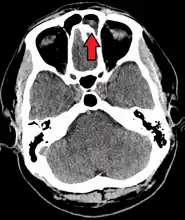

The proximity of the brain to the sinuses makes the most dangerous complication of sinusitis, particularly involving the frontal and sphenoid sinuses, infection of the brain by the invasion of anaerobic bacteria through the bones or blood vessels. Abscesses, meningitis, and other life-threatening conditions may result. In extreme cases, the patient may experience mild personality changes, headache, altered consciousness, visual problems, seizures, coma, and possibly death.[12]

Sinus infection can spread through anastomosing veins or by direct extension to close structures. Orbital complications were categorized by Chandler et al. into five stages according to their severity (see table).[20] Contiguous spread to the orbit may result in periorbital cellulitis, subperiosteal abscess, orbital cellulitis, and abscess. Orbital cellulitis can complicate acute ethmoiditis if anterior and posterior ethmoidal veins thrombophlebitis enables the spread of the infection to the lateral or orbital side of the ethmoid labyrinth. Sinusitis may extend to the central nervous system, where it may cause cavernous sinus thrombosis, retrograde meningitis, and epidural, subdural, and brain abscesses.[21] Orbital symptoms frequently precede intracranial spread of the infection . Other complications include sinobronchitis, maxillary osteomyelitis, and frontal bone osteomyelitis.[22][23][24][25] Osteomyelitis of the frontal bone often originates from a spreading thrombophlebitis. A periostitis of the frontal sinus causes an osteitis and a periostitis of the outer membrane, which produces a tender, puffy swelling of the forehead.

The diagnosis of these complications can be assisted by noting local tenderness and dull pain, and can be confirmed by CT and nuclear isotope scanning. The most common microbial causes are anaerobic bacteria and S. aureus. Treatment includes performing surgical drainage and administration of antimicrobial therapy. Surgical debridement is rarely required after an extended course of parenteral antimicrobial therapy.[26] Chronic sinus infections may lead to mouth breathing, which can result in mouth dryness and an increased risk of gingivitis. Decongestants may also cause mouth dryness.[27]